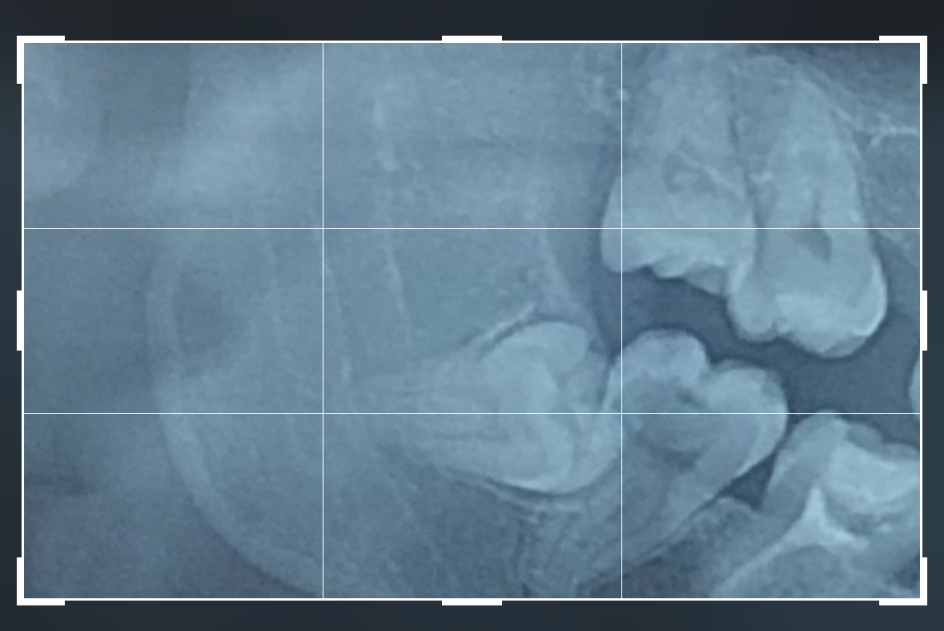

Здравейте, сложно е да прегледам толкова много страници и имам нужда наистина от хора с опит. Долу в дясно мъдрец. Не е избил изобщо, расте към корена на другия зъб и дори му е направил кариес. Трябва да го премахна оперативно. Огромния проблем е, че назад в челюстта ми няма място за голям разрез и може да се наложи и настрани. Страхът е голямо нещо, но трябва да го направя. Коментирала съм с хирург в ео дент, но никой не ми казва цена. Как стоят нещата в лицево-челюстната на ВМА. Обясниха ми, че има вероятност и да ми засегнат някой нерв… объркана съм къде да ида, все пак са зъби и наистина ме е страх от усложнения

Обади в отделението и попитай. Моят мъдрец беше същият. Хубавото е, че твърда цената там, независимо колко е сложен случаят, за разлика от частните клиники